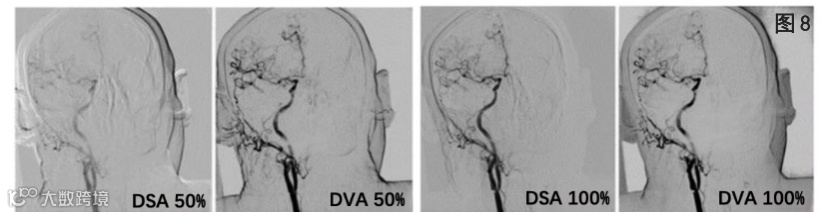

图7.对比噪声比(CNR)结果/单幅图像质量评价结果。(盲法随机,采用4级Likert评分)

研究表明100%碘化造影剂方案,DVA的图像质量明显高于DSA;100%造影剂剂量的DSA与50%造影剂剂量的DVA的图像质量没有明显差异。比较有趣的是,61%的研究人员更喜欢50%造影剂量的DVA图像,而不是100%造影剂量的DSA图像。